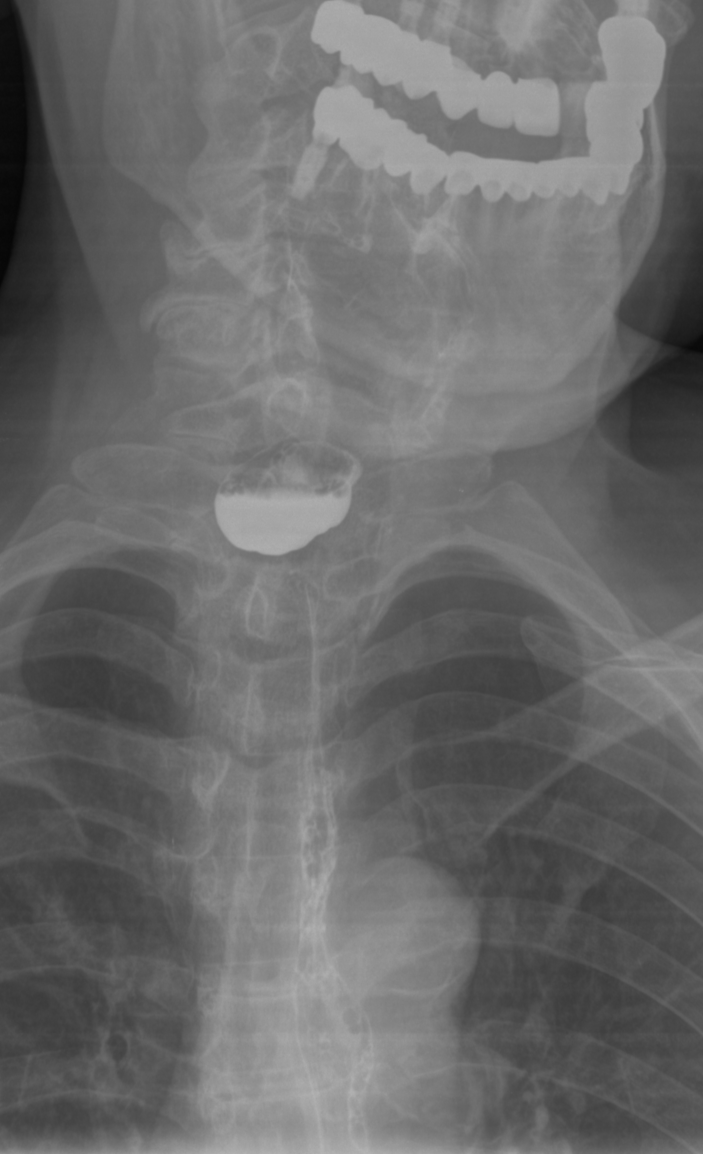

IMG20251208130343.jpg

Где пиздецома?

>>327474857

Бля то ли субтотальная пневмония, то ли осумкованный плеврит такой. всё нахуй забыл уже с рентгенологии